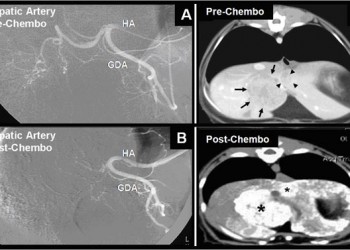

Chimioembolizarea hepatică este o procedură modernă de tratament a tumorilor hepatice (cancer hepatic primitiv sau metastaze hepatice), care poate fi utilizată în cazul în viagrastoresa prezintă contraindicații pentru intervenția chirurgicală. Chimioembolizarea se realizează în laboratorul de radiologie intervențională și presupune întreruperea vascularizației tumorii, care duce la necroza țesutului neoplazic.

Chimioembolizarea presupune întreruperea vascularizației tumorale prin injectarea selectivă în artera hepatică a unui agent citostatic și a unui agent de ocluzie. Metoda nu distruge decât țesutul tumoral, care prezintă doar vascularizație din artera hepatică, spre deosebire de parenchimul hepatic normal, care prezintă dublă vascularizație, prin artera hepatică și vena portă.

Sub ghidaj arteriografic, se cateterizează selectiv artera hepatică și se introduce materialul emboligen (citostatic+agent fixator), a cărui compoziție este stabilită de medicul oncolog. Se realizează mai multe ședințe, fiecare cu durata a 1-2 ore. Urmărirea eficienței se face prin dozarea AFP (alfa-fetoproteinei) și prin CT abdominal.

Chimioembolizarea este recomandată pacienților cu tumori hepatice primare inoperabile sau metastaze (determinări secundare) de la un cancer colorectal, cancer mamar, sarcom, carcinoid sau alte tumori neuroendocrine, cancer pancreatic insular, melanom ocular sau tumori vasculare. Este o metodă paliativă bună, care oferă un plus de supraviețuire pacienților terminali. Procedura poate fi repetată de câte ori este necesar pentru controlul bolii tumorale. Extinderea necrozei tumorale obținute prin chimioembolizare se evaluează cu CT/IRM cu substanță de contrast și ecografie Doppler color la 6-12 săptămâni de la efectuarea chimioembolizării. Rata recurențelor este de 18% la 1 an și de 30% la 2 ani. Supraviețuirea este de 54-88% la 1 an și de 18-50% la 3 ani.

Chimioembolizarea asigură reducerea sau stabilizarea tumorii în peste 60% din cazuri.